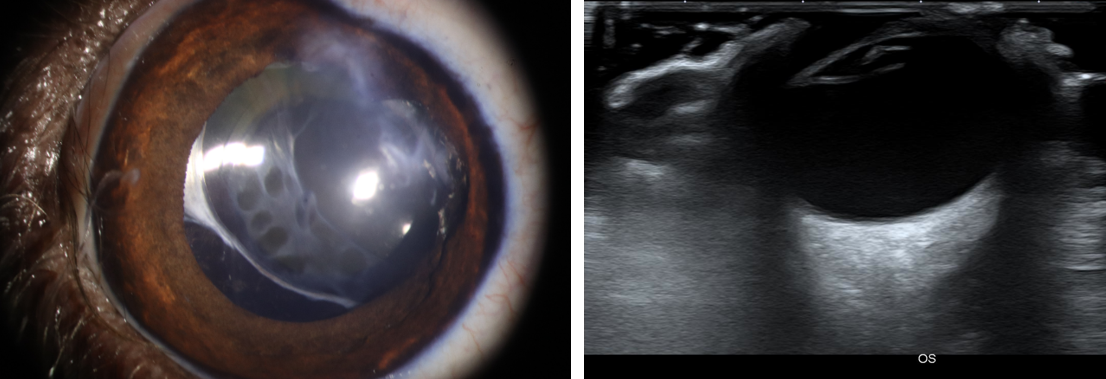

.png)

사진4. 이전 시력 소실, 안압 상승 확인되었으나 수술적 교정 후 이상 증상 없음. 수술 후 5개월 세극등 현미경 사진 (좌). 초음파 검사상 후안부 등 안구 조물에 이상 확인되지 않음 (우).